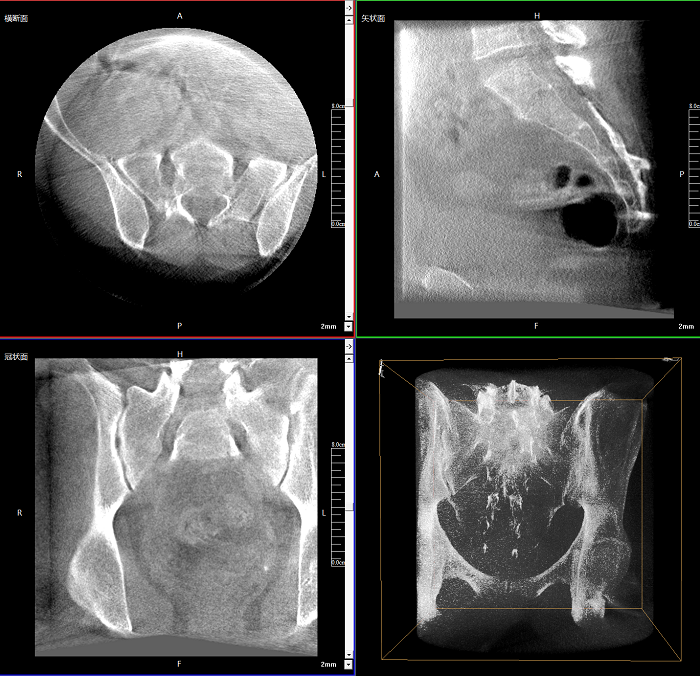

三維成像 全面觀察

任意視角、任意切面觀察

術(shù)中實(shí)時(shí)生成橫斷面、矢狀面、冠狀面及三維影像,可在任意切面、任意角度評(píng)估植入物和解剖結(jié)構(gòu)的相對(duì)位置。

Clinical picture

臨床圖片